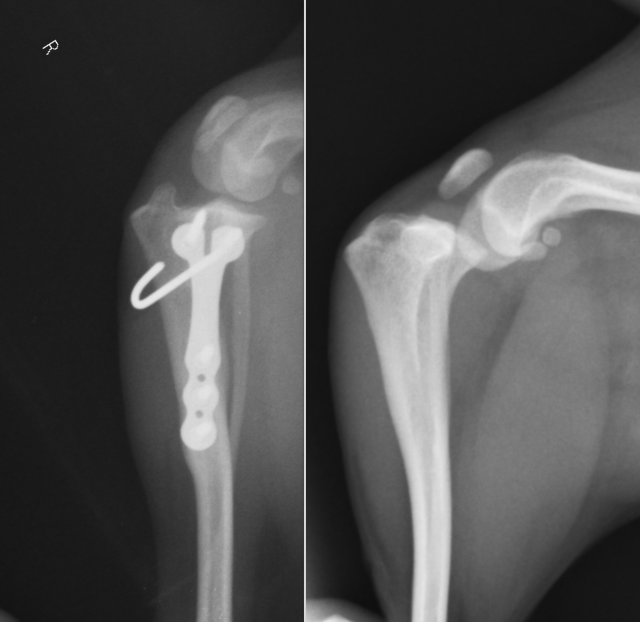

フレンチブルドッグの症例です。TPAが高く回転距離が長くなっています。TPAが高い症例はTPLOの合併症が起きやすたいめ、その手術計画は注意して行う必要があります。

近年では小型犬の前十字靭帯断裂も増えてきています。背景には膝蓋骨内方脱臼によるものが関与していると考えられます。このレントゲンも4kgほどのトイプードルです。